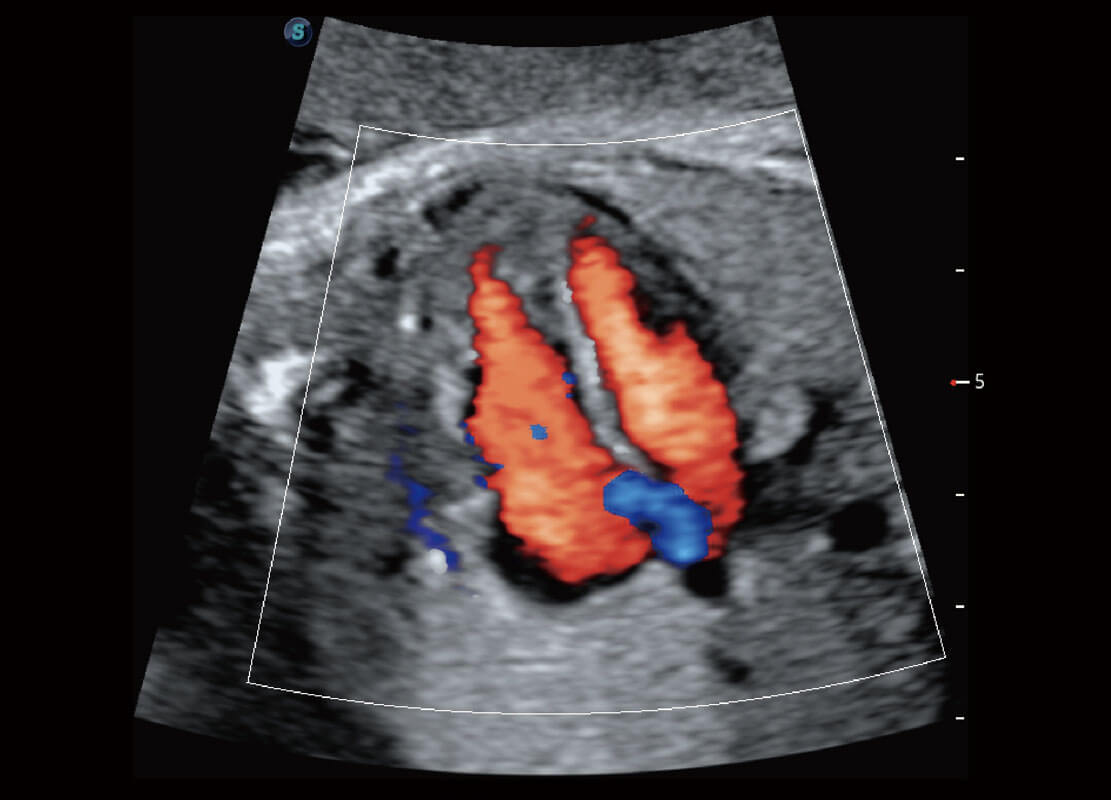

• 胎儿体循环